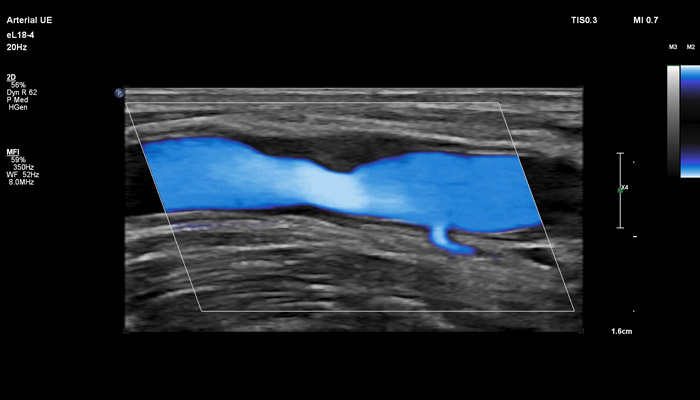

Инновационный датчик eL18-4 работает в частотном диапазоне 2-22МГц, что открывает широкий спектр возможностей его применения в ультразвуковой диагностике. Универсальность датчика позволяет использовать его для комплекса ультразвуковых исследований в таких областях, как: молочная железа (с функцией эластографии сдвиговой волной), поверхностные органы (с функцией эластографии сдвиговой волной), опорно-двигательный аппарат, исследования сосудов (с автоматическим измерением толщины сосудистой стенки), органы брюшной полости, исследования в педиатрии, пренатальная диагностика.

Бесспорное достоинство датчика – его универсальность. УЗ-аппараты, оснащённые eL18-4, помимо акушерства можно использовать для обследования щитовидной железы, молочных желёз, сосудов шеи, рук и ног, органов мужской репродуктивной системы, брюшной полости и малого таза детей и подростков.

Линейный матричный датчик eL18-4 поддерживает режим высокочувствительной визуализации кровотока (Philips MicroFlow Imaging), новый запатентованный метод, который обеспечивает инновационный подход к оценке сосудистого русла. Визуализация MicroFlow преодолевает многие барьеры, связанные с традиционными методами обнаружения кровотока в малых сосудах, обеспечивая высокое разрешение при минимальных артефактах. Метод MicroFlow Imaging поддерживает высокую частоту кадров и качество изображения, применяет инновационные методы сокращения артефактов. Варианты вычитания 2D-изображений, смешивания и параллельного отображения обеспечивают превосходную визуализацию в различных клинических случаях.